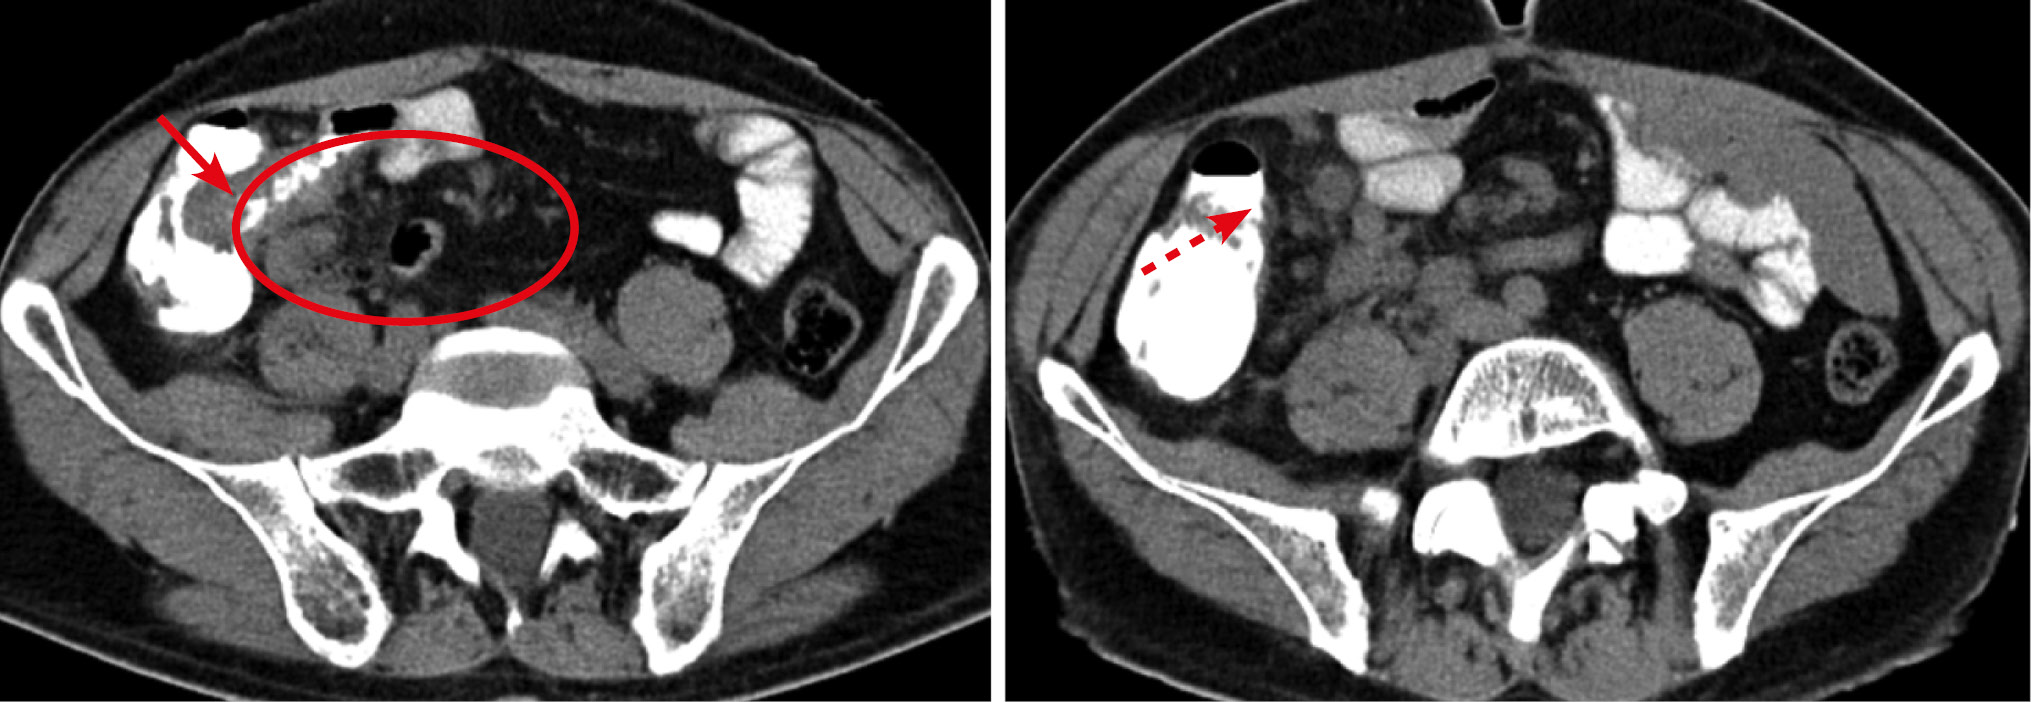

Рис. 10. Больной, 48 лет. МСКТ: саркома подвздошной кишки

Примечание. А — нативное исследование, Б — артериальная фаза контрастного усиления. По брыжеечному краю стенки подвздошной кишки наблюдается сегментарное утолщение стенки (стрелка), которое при контрастном усилении накапливает контрастный препарат равномерно и трансмурально. В прилежащей части брыжейки определяется разрастание элементов опухолевой ткани.

Метастатическое поражение висцеральных листков брюшины вызвало утолщение стенки кишки у 16 (18,6%) больных. Причинами вторичного поражения брюшины чаще служили опухоли желудочно-кишечного тракта и поджелудочной железы. На томограммах метастатическое поражение брюшины проявлялось отложением солидных масс в виде плоскостных или бугристых утолщений на покрывающих кишечник серозных оболочках (рис. 11). При прогрессировании определялась инвазия опухоли в стенку кишки с утолщением стенки и сужением просвета, что вызывало кишечную непроходимость. Поражение чаще носило множественный характер. По протяженности сегментарные утолщения (67%) встречались чаще фокальных (33%), с прогностическим значением положительного результата 20 и 12,2% соответственно. Распространенные поражения сопровождались скоплением жидкости в брюшной полости. При контрастном усилении солидные массы на серозных оболочках характеризовались повышенным контрастным усилением.

Рис. 11. Больная, 68 лет. МСКТ: рак желудка. Метастатическое поражение серозных оболочек. Кишечная непроходимость. Артериальная фаза контрастного усиления

Примечание. В антральном отделе желудка определяется опухоль (пунктирная стрелка). Визуализируются неравномерные утолщения стенки кишки, обусловленные вторичным поражением серозных покровов (стрелки).